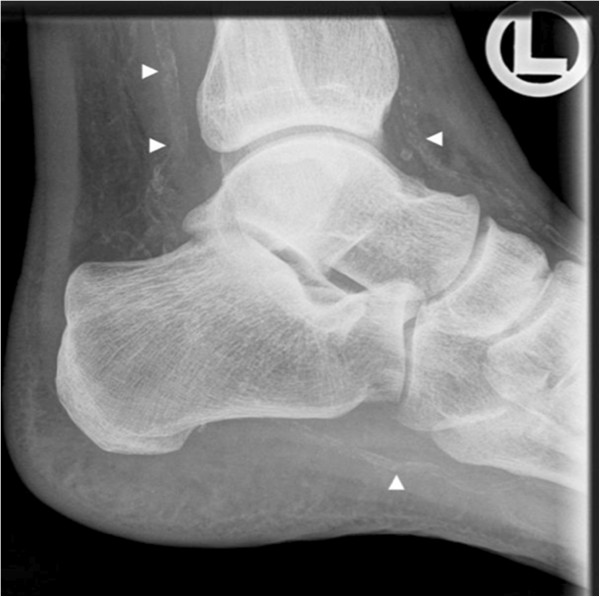

X-ray examinations of the patient’s hands and right foot (Figure 3) for joint pain revealed advanced calcification of the anterior and posterior tibial and plantar arteries and the radial artery, a finding to be expected in a patient with long-lasting kidney disease. Duplex ultrasound examination of peripheral muscular arteries (Figure 4) confirmed the presence of abundant vessel wall calcifications. The arterial blood flow signal was normal without signs of vascular stenosis. Computed tomography of the coronary arteries revealed severe calcification with an Agatston score of 782.5 corresponding to the 99th percentile of age and gender matched controls [9]. Co-illustrated slices of the aorta were free of calcification.

Figure 3.

X-ray of right ankle. Severe calcification of the anterior and posterior tibial and plantar arteries is evident (white arrows).